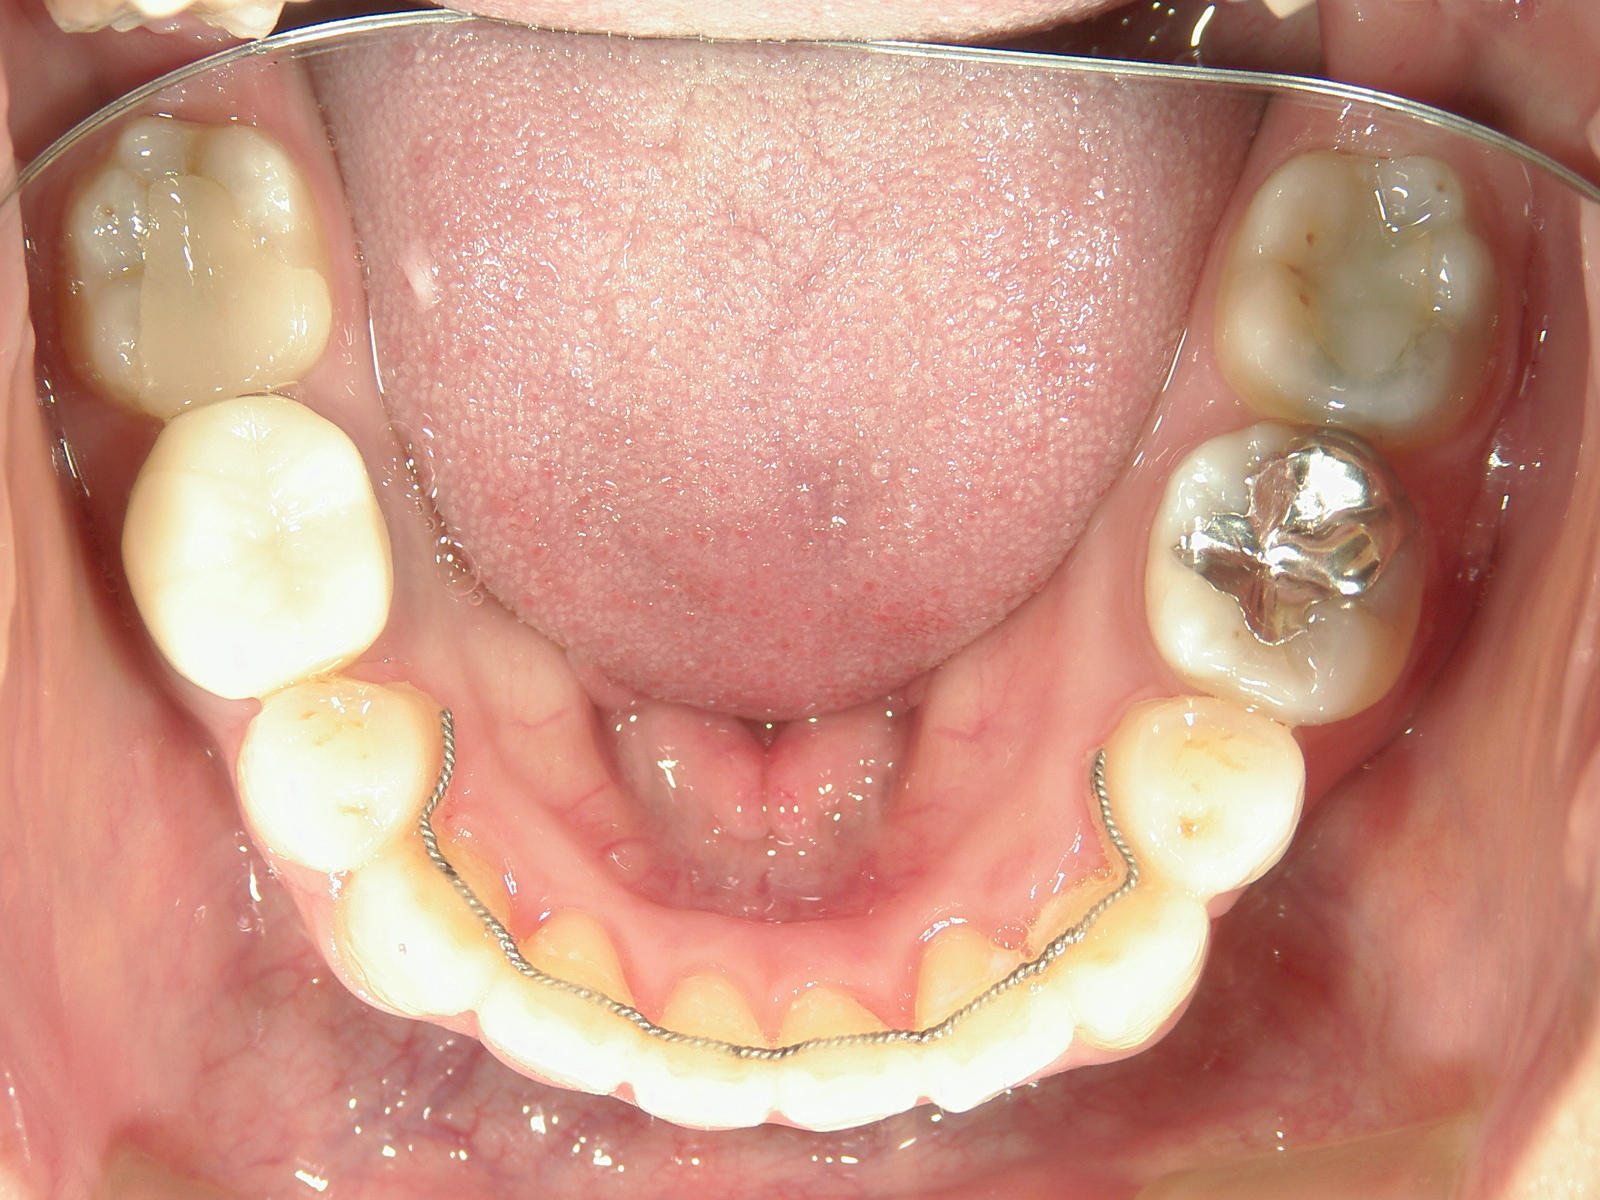

左右上 第一小臼歯(2本)、左右下 第二小臼歯(2本)を抜歯。

矯正装置(BH・QH)を併用。

ミニインプラント、アップライトスプリングを併用。

右下大臼歯(2本)をZ冠、E-MAX(On)に変更。